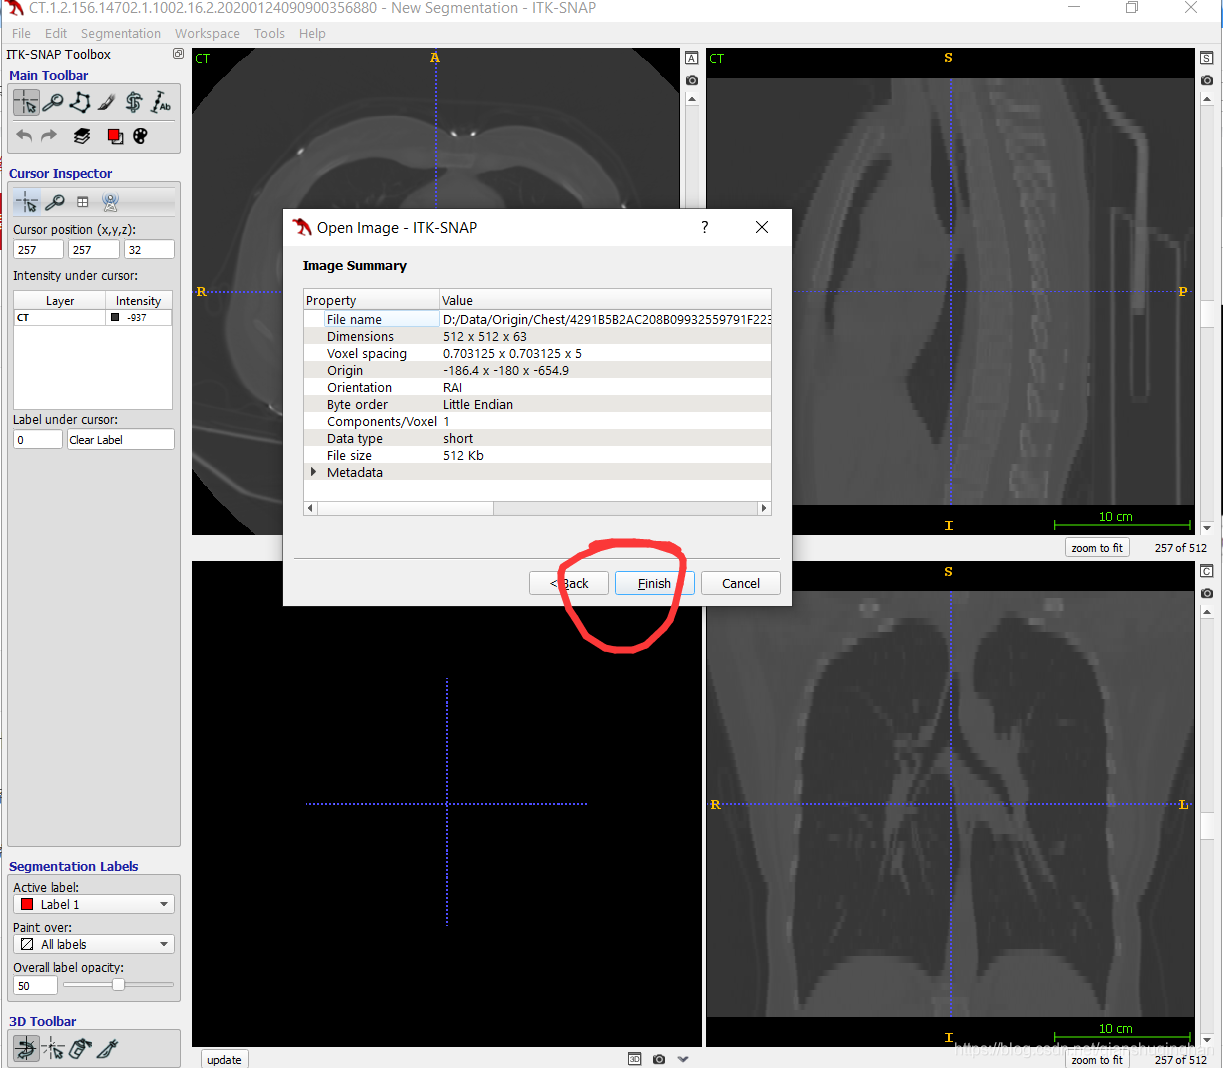

导入图像

可采用拖拽、或者File->Open Main Image两种方式导入图像(支持dicom,nifity等格式文件)

如文件夹下含多个图像序列,此处会显示多个序列列表,选中待勾画序列,电极下一步即可导入,最后点击finish